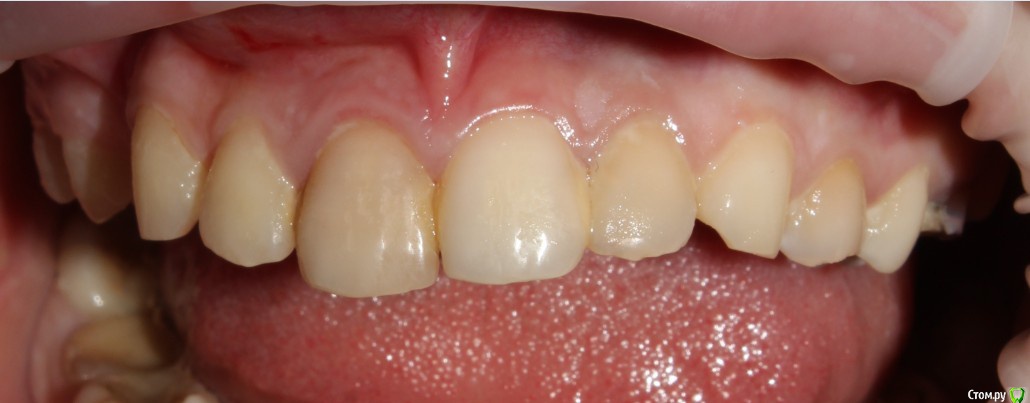

Рустам Опубликовано 4 ноября, 2016 Поделиться Опубликовано 4 ноября, 2016 Добрый вечер коллеги! Вчера обратилась пациентка (19 лет) с жалобой на подвижность коронки 1.1 зуба.Коронку убрал, скол достаточно глубоко (2-3мм ниже уровня десны), в зоне БШ. Удлинение во фронте не вариант на мой взгляд. Феррул не получить. Имплантолог ввиду возраста в имплантации отказывает.Пока сделал временный зуб на униметрике. КТ пока не делали. Записал на повторную консультацию. Как бы вы поступили в данной ситуации Ссылка на комментарий

229KAMA Опубликовано 4 ноября, 2016 Поделиться Опубликовано 4 ноября, 2016 Возможно вы не так выразились но коронки ни на одном из представленных снимков я неувидел.Теперь чтобы сделал я , учитывая гигиену по снимкам и количество зубов и качество пломб предположу как и уменя в госе я бы поработал "спасателем" как обычно за неимением финансовой возможности у больного , а может и особого желания заниматься зубами.1-подрезалбы десну по вестибулярке.2-времен.востан.коронк. часть зуба через анкерный штифт.(хорошо его зафиксир)чтобы попробовать немного вытянуть коронарно.(потреб времен.конечно и за свой счет ну хотябы частично.)3-после того как зуб перем корон.поработать с десной (может и с биологической шириной) по вестибулярке для того чтобы спрогнозировать минималный ферул. Ну тоже часть финанс нагр на мне.4-дальше если ферул получил то ВКВ и далее как обычно коронк.Да знаю нормальный врач сразу мне СКАЖЕТ что все это мартышкин труд надо ВСЕ как положенно , удалить может одномоментно винт и т.д.Но мне часто приходиться пахожие ситуации разруливать и зная как правильно НАДО , по обстоятельства разным приходиться становиться "спасателем" всегда заранее поциентам обьясняю что это не по протоколу. Только после этого пытаюсь оттянуть смертный приговор зуба. Некоторые возврашаются накопив средства чобы все сделать правильно и меня это радует , что кто то правильно понял мою информацию как надо правильно. Както так действую. 1 Ссылка на комментарий

RuStom Опубликовано 5 ноября, 2016 Поделиться Опубликовано 5 ноября, 2016 Возможно вы не так выразились но коронки ни на одном из представленных снимков я неувидел. Вы не видите коронку зуба??? 1 Ссылка на комментарий